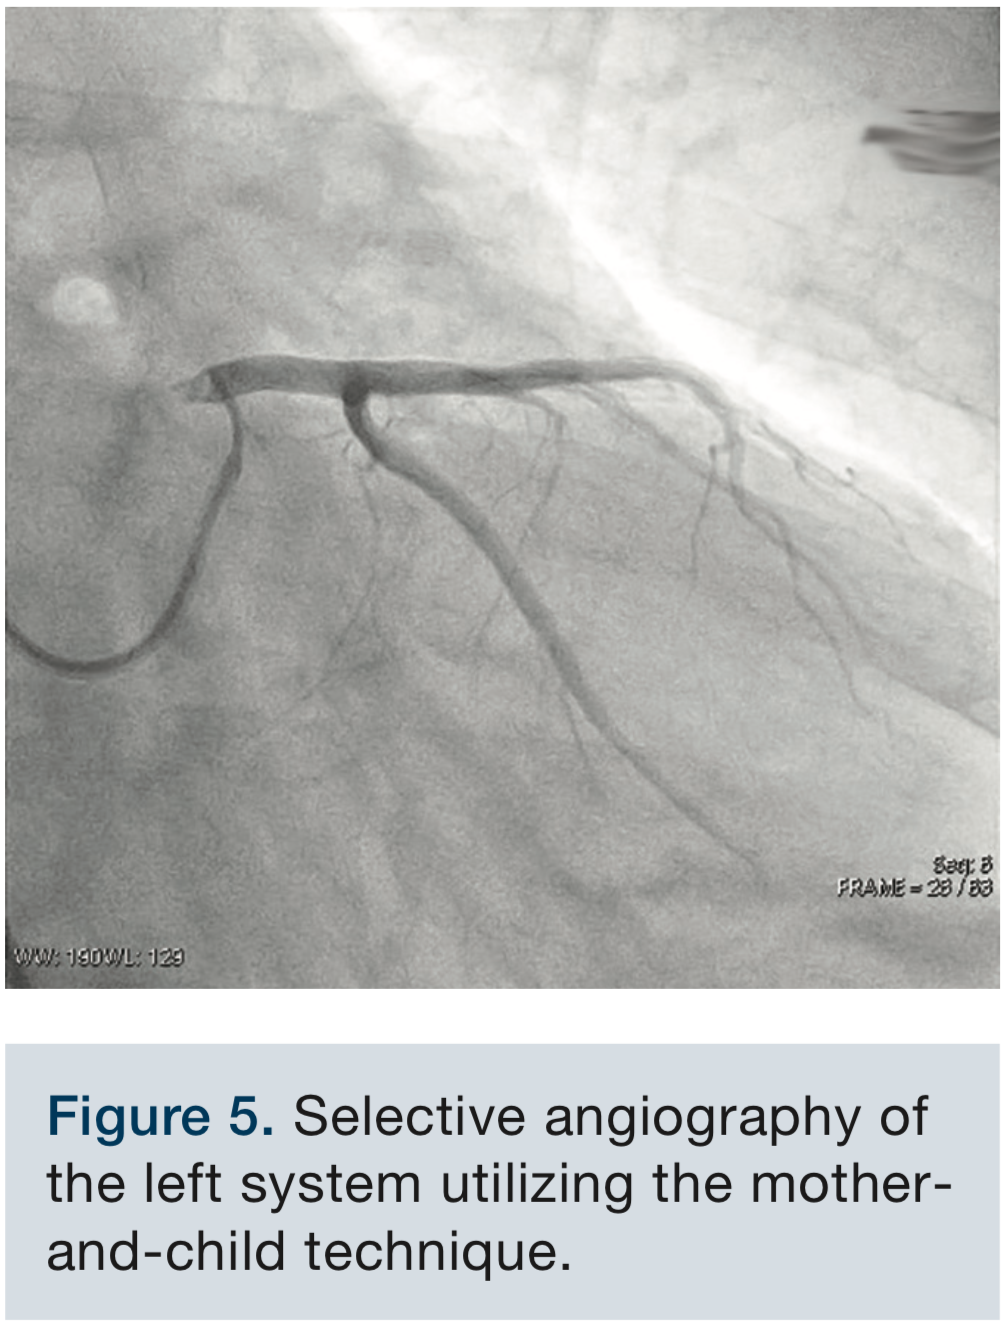

Given the appearance of the root and the inability of the AL3 to reach the ostium, a 4 French multipurpose A2 (MP-A2) diagnostic catheter was advanced through a 6 French AL3 guide catheter utilizing a “mother-and-child” technique and was successful in engaging the left main ostium (Figure 4). Selective angiography of the left system was performed (Figure 5, Video 3). Angiography of the right coronary was performed using a Judkins right 5 (JR5) catheter.

The mother-and-child technique is commonly used in interventional cardiology, especially during interventions on distal lesions, chronic total occlusions, and in unusual anatomy.1 However, the utilization of this technique is not as common for diagnostic angiography. In the published case reports using the mother-and-child technique, the most common inner (“child”) catheter used was the GuideLiner catheter (Vascular Solutions). In contrast, in our case we used a multipurpose A2 catheter, offering greater directional control of the catheter in order to direct it across the aortic root. The combined 6F AL3 and 4 French MP catheter should be manipulated with appropriate caution to avoid potential trauma to the aortic root and/or coronary ostium. In addition, the catheter is stiffer than the GuideLiner catheter and as such, this maneuver should be carried out with greater caution.

This case uses a novel technique of mother-and-child catheterization utilizing a 4 French multipurpose catheter within a 6 French AL3 guide catheter to successfully engage the left main coronary artery in a dilated aortic root, with an additional challenge posed by a tortuous iliac artery. This technique, which utilizes a stiffer, more directional catheter, allows for controlled engagement of the left main in patients with difficult anatomy, especially dilated ascending aortas.